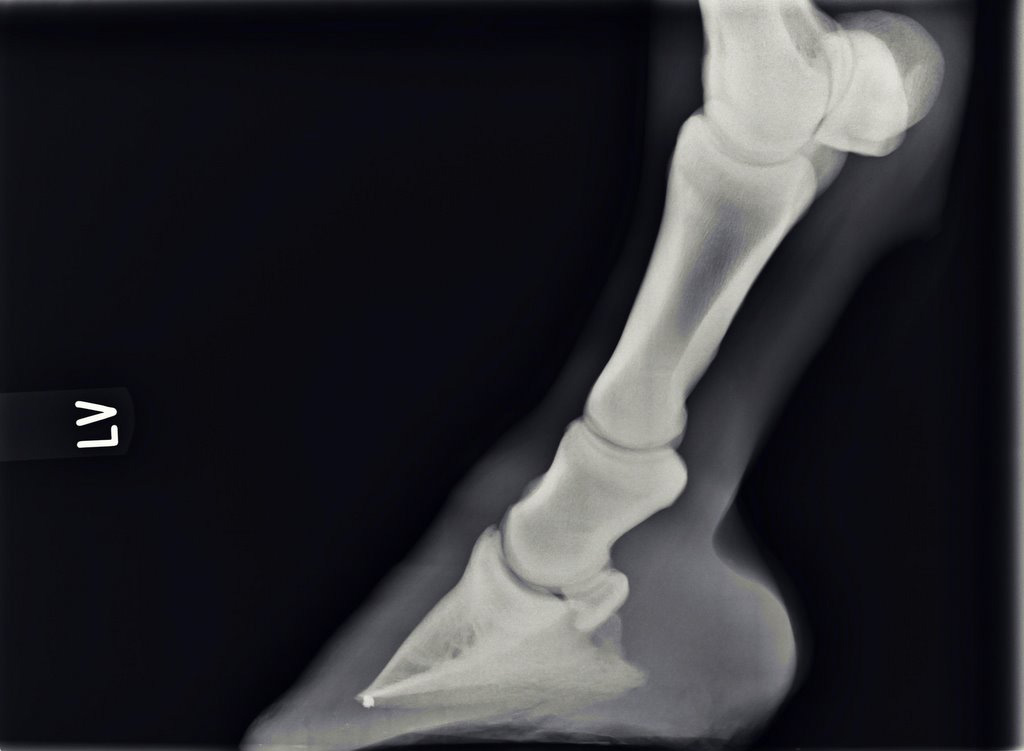

Illustrative Mindeststandardaufnahmen zur Beurteilung nach dem Röntgenleitfaden: